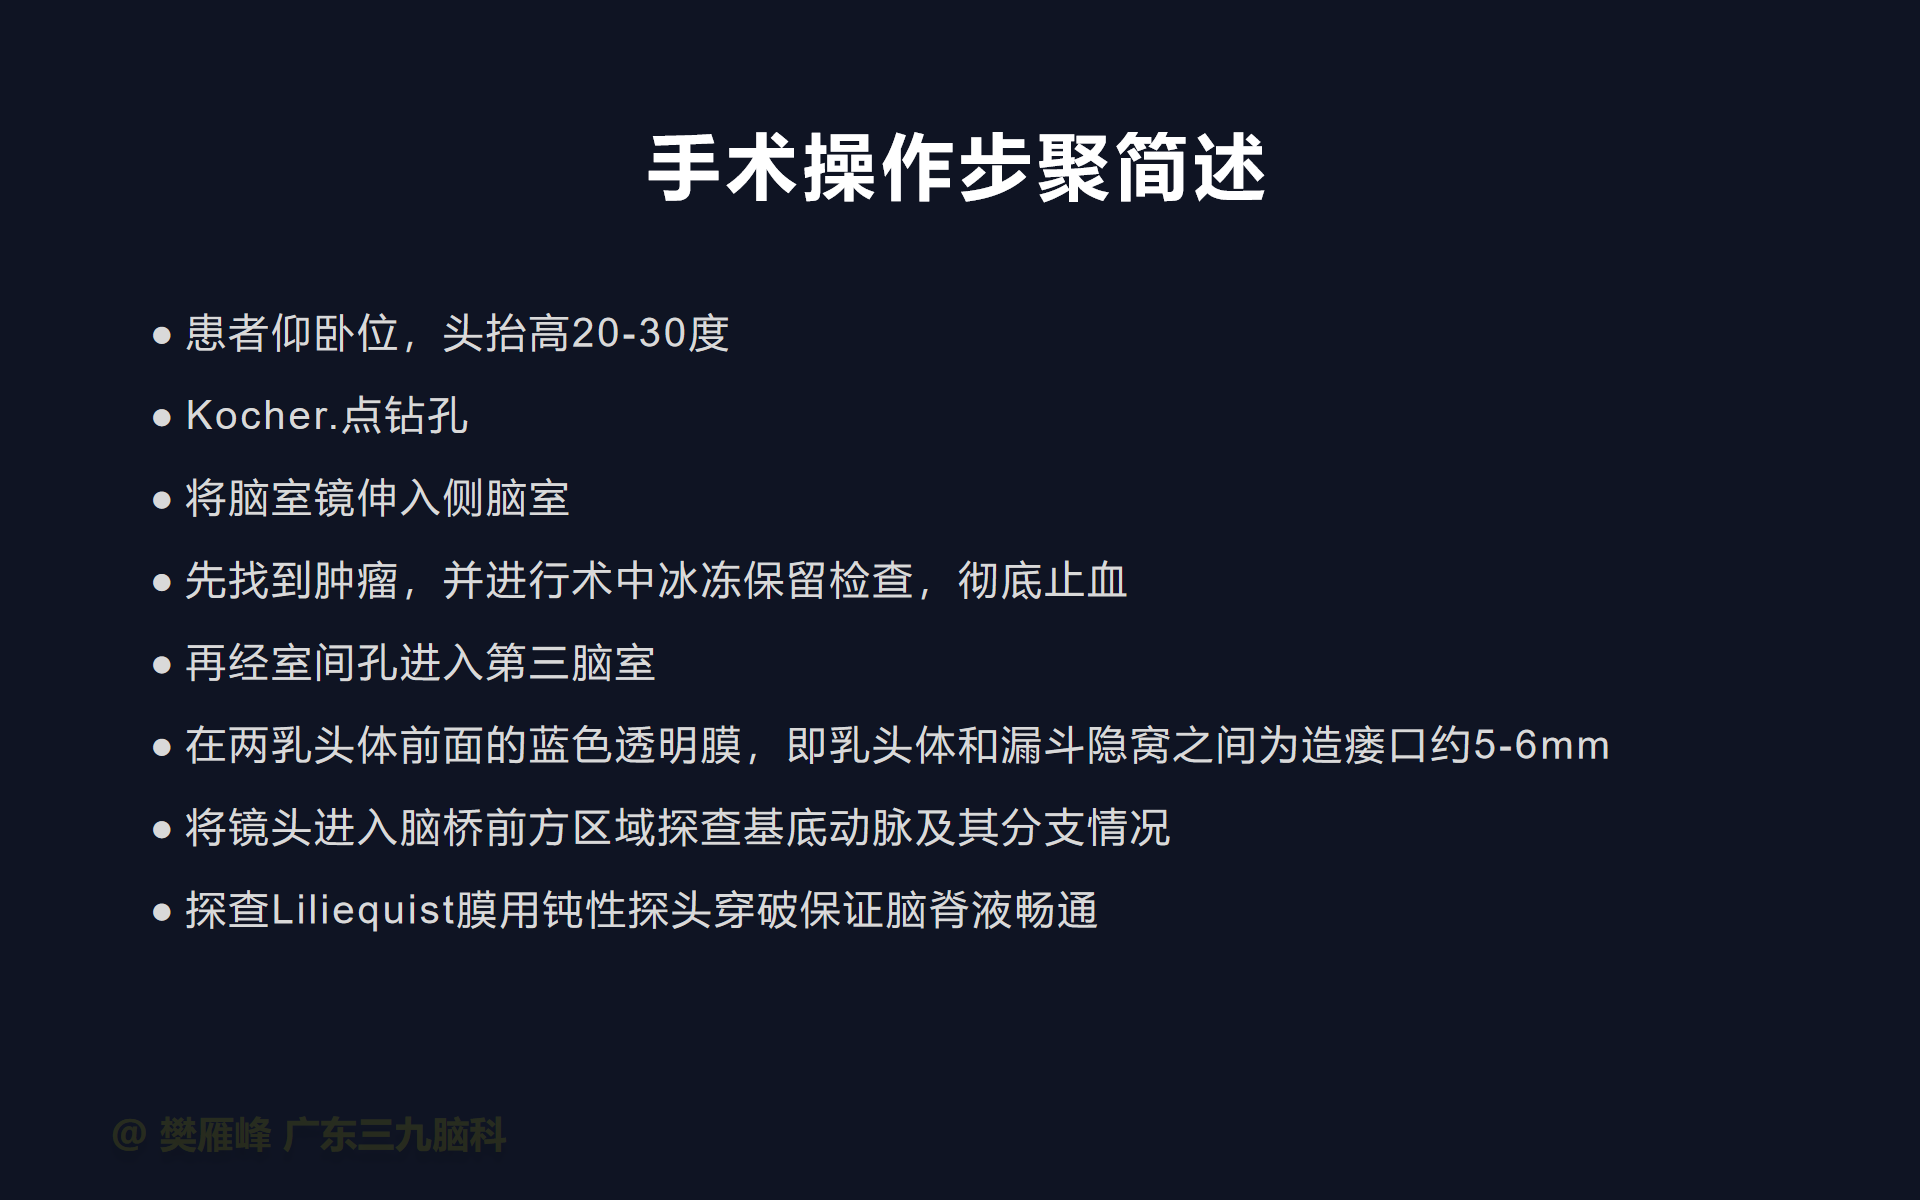

在这个二维手术视频中,展示了2例神经内镜下三脑室底造瘘+活检治疗三脑室后部肿瘤的方法。患者均为三脑室后部病变导致的梗阻性脑积水,病理结果1例为生殖细胞瘤,1例为淋巴瘤,在经过术后的放化疗病情均得到控制,生活质量满意。我们展示了安全的病变活检和第三脑室造瘘的技术要点,以最大限度减少术后继发脑积水和早期并发症。